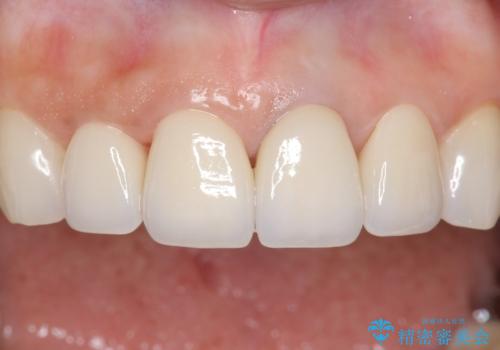

5年前のクラウン装着時と比較したところ、歯肉が成熟し歯間乳頭ができており、より天然歯のように自然に見えました。

患者様の良好なセルフケアと精密な適合の良いクラウンにより、歯肉の腫脹や退縮も認められませんでした。

5年前に行った治療に大変ご満足頂き、他の部位も治療やホワイトニングを希望して下さいました。

人工のダイヤモンドにも用いられるジルコニアは、セラミック系素材の中でも圧倒的に丈夫かつ審美的で、劣化しにくく口腔内でも長期間安定した状態を保つことができます。

クラウンの種類:ジルコニアオールセラミッククラウン スタンダード